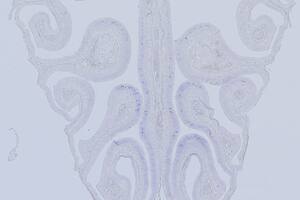

Genética

Estudo mostra por que o olfato varia ao longo da vida

Estudo mostra por que o olfato varia ao longo da vida

Por Maria Guimarães